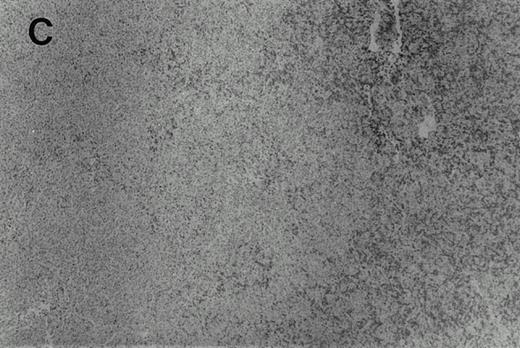

Immunohistochemistry of CD3 in case 1: (A) low (40×), (B) high (400×). CD3+ T cells are associated with clusters of H-RS cells, often forming a ring around the H-RS cells. Inset shows CD30+ H-RS cells. Immunohistochemistry of MB2 in case 2: (C) low (40×), (D) high (400×). MB2+ CLL cells are present around a nodule of HD. H-RS cells are admixed with T cells and histiocytes and only scattered MB2+ small lymphocytes are present.